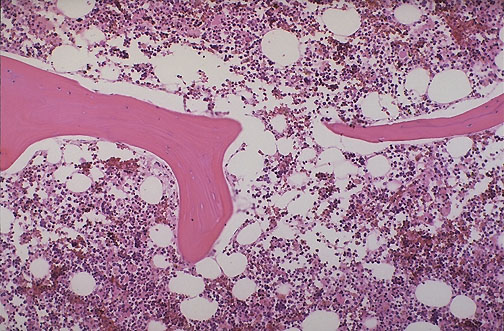

Normal vertebral bone and marrow is demonstrated at low power microscopically. Note the size and number of bone spicules.